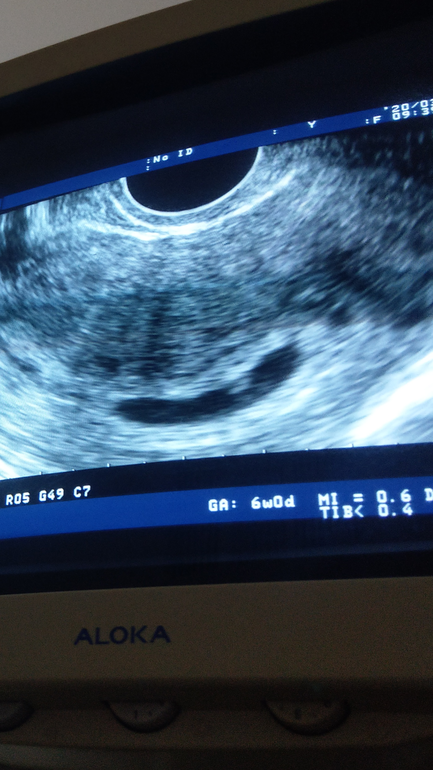

Плодное Яйцо

Вопросы про УЗИ, обследования и анализы: что, где, как, когда?У кого-нибудь было такое плодное яйцо? Сегодня была на узи. Сердце бьётся. Ктр 6.5 мм. Яйцо большое и вытянутое. Спросила я про тонус ,она пробормотала,мол ну да ,может быть ... Спросила мне надо на прием , лекарства? Сказала ничего страшного нет ... Купила сама Магне Б6, иногда тянет живот ,лучше попью

Там жк если вытянуто хитро измеряется, типа и длину и ширину и среднее высчитывается. С сыном было, 10х4 яйцо и ср писали 7 мм

Пульсация вроде есть, а прослушать такого маленького она не смогла) в 8 контроль))